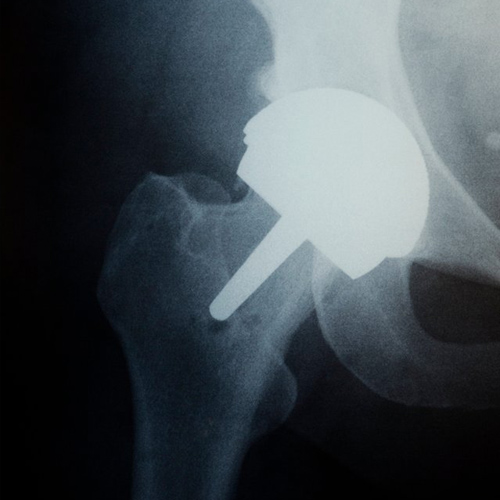

인공관절수술

인공관절수술은 손상되거나 퇴행성 변화가 있는 관절을 인공 관절로 대체하는 수술입니다.

주로 무릎, 엉덩이, 어깨 관절에서 시행됩니다.

인공 재질로 된 관절로 바꾸어주는 수술입니다.

인공관절수술 과정

X-ray, CT/MRI 등의 정밀 검사를 통해 손상된 관절의 상태와 다리 축 변형 정도를 정확하게 진단합니다. 로봇 또는 컴퓨터 내비게이션 수술을 할 경우, 이 데이터를 기반으로 인공관절의 최적 크기, 위치, 각도를 미리 설정하고 가상 시뮬레이션을 통해 수술 계획을 완성합니다.

절제된 뼈의 표면에 맞추어 금속 및 특수 플라스틱 재질로 구성된 **인공관절 구성품(임플란트)**을 삽입하고 단단하게 고정합니다.